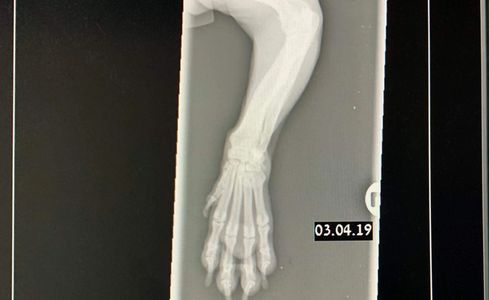

Our surgeries are carried out in our new state of the art facility which comprises a large prep room and two theatres. Surgeries are done Monday to Friday after our Consults Clinic.

Our daily surgery list would usually range from routine neutering of cats, dogs, rabbits, ferrets and guinea pigs. There would also be dental work cases on the list which would include x-rays, descaling, polishing and where necessary extractions.

We also carry out cruciate repair surgery.

Not all surgeries are planned and on occasions emergencies present themselves, an example being Cesarean Sections.